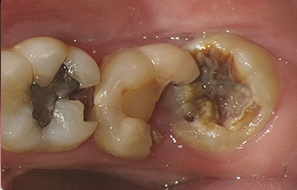

本院為40年 口腔外科專業診所,主攻”安全、無痛”、專拔高風險(牙根與神經交錯或緊貼)、高難度、深度阻生智齒手術。

為了健保患者拔智齒的安全,遠離唇麻、舌麻、口鼻竇炎、大出血...等併發症,

☆本院特別巨資增設 ”千萬級3D AI透視電腦斷層”,並配合“成骨膠原蛋白”施作 (上述兩項目前健保無給付),讓您遠離神經傷害、口鼻竇(炎)相通...等併發症,除健保之外,難免會有避免併發症風險的自費項目,網路上經常會有看到智齒拔完後唇麻、舌麻、口鼻竇相通等併發症,在本院嚴格自我要求下,此類併發症在本院幾乎趨近於零。